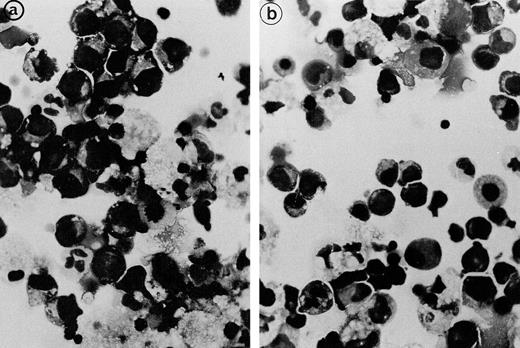

Fig. 4.

Light microscopical aspect of the erythroblasts cultured from patient 2 bone marrow. (a) In the presence of autologous serum: The erythroblasts are closely apposed to each other with occasional nonbasophilic areas present at their junction, mimicking the morphology of the bone marrow smears. (b) In the presence of a control serum: The grown erythroblasts are scattered and individually disposed on this cytospun preparation and do not display the characteristic abnormalities of the disease.

The erythroblastic synartesis could be reproduced in vitro: indeed, erythroblast cultures established with bone marrow progenitors from cases 2 and 3 displayed similar morphological abnormalities to those observed in vivo (Fig4a, see page 3686). Crossed culture experiments using the patient erythroblasts grown in the presence of their own serum or of a control serum, or using erythroblasts of a control subject grown in the presence of the patient sera (see Table1) were performed and gave the following results: the erythroblast abnormalities reproduced in culture in the presence of autologous serum were absent when the culture was performed with a control AB serum (Fig 4b). Electron microscopy confirmed these findings, showing that the same intercellular junctions were observed when the patient erythroblastic progenitors were cultured with autologous serum, but that they were absent when the culture was performed in the presence of a control serum. These abnormalities were not reproduced in vitro when the erythroblasts were grown in the patient sera that had been IgG depleted. This allowed us to conclude that the synartesis was caused by an IgG component. Further confirmation was given by the observation that cultured normal erythroblasts displayed authentic synartesis when grown in the presence of patient to serum. Finally, the IgG fractions from the patients were added to normal serum at a concentration of 2 g/L and were able to induce typical synartesis on control erythroblasts grown in this preparation (Fig 5).